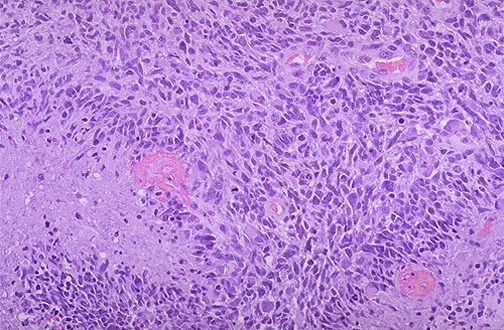

Glioblastoma - pseudo pallisading cells, cystic degeneration, anaplastic, necrosis

Primary: xPTEN, EGFR^, xCDKN2A

Secondary: xTP53, IDH1/2 (longer survival), PDGFR^

Glioblastoma